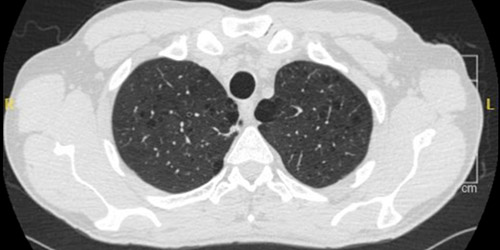

CT scan of emphysema in a person living with HIV